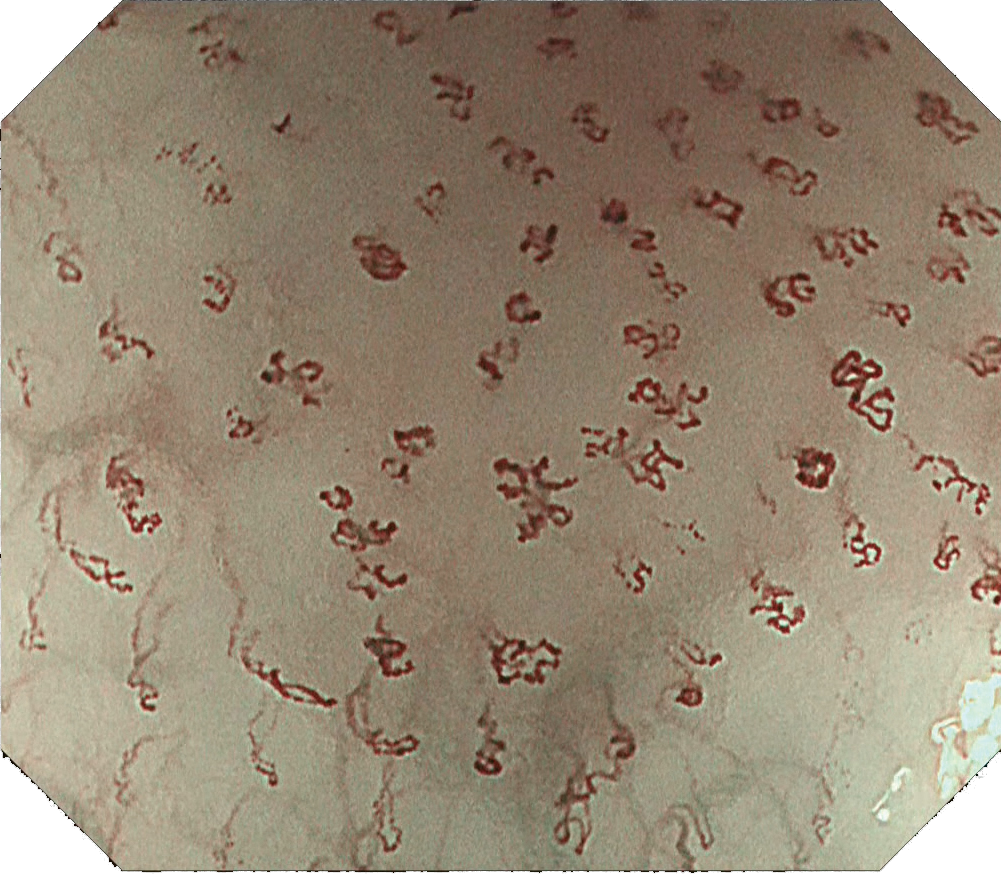

Endocyto観察原理

適切な薬剤で細胞核を染色した後、対物レンズを観察部位に接触させ粘膜表層の細胞を観察します。ライトガイドから出た光が生体内部に散乱光として取り込まれることにより、粘膜表層の細胞組織等が観察できます。

EC観察とEC-NBI観察

EC観察

腫瘍(食道)